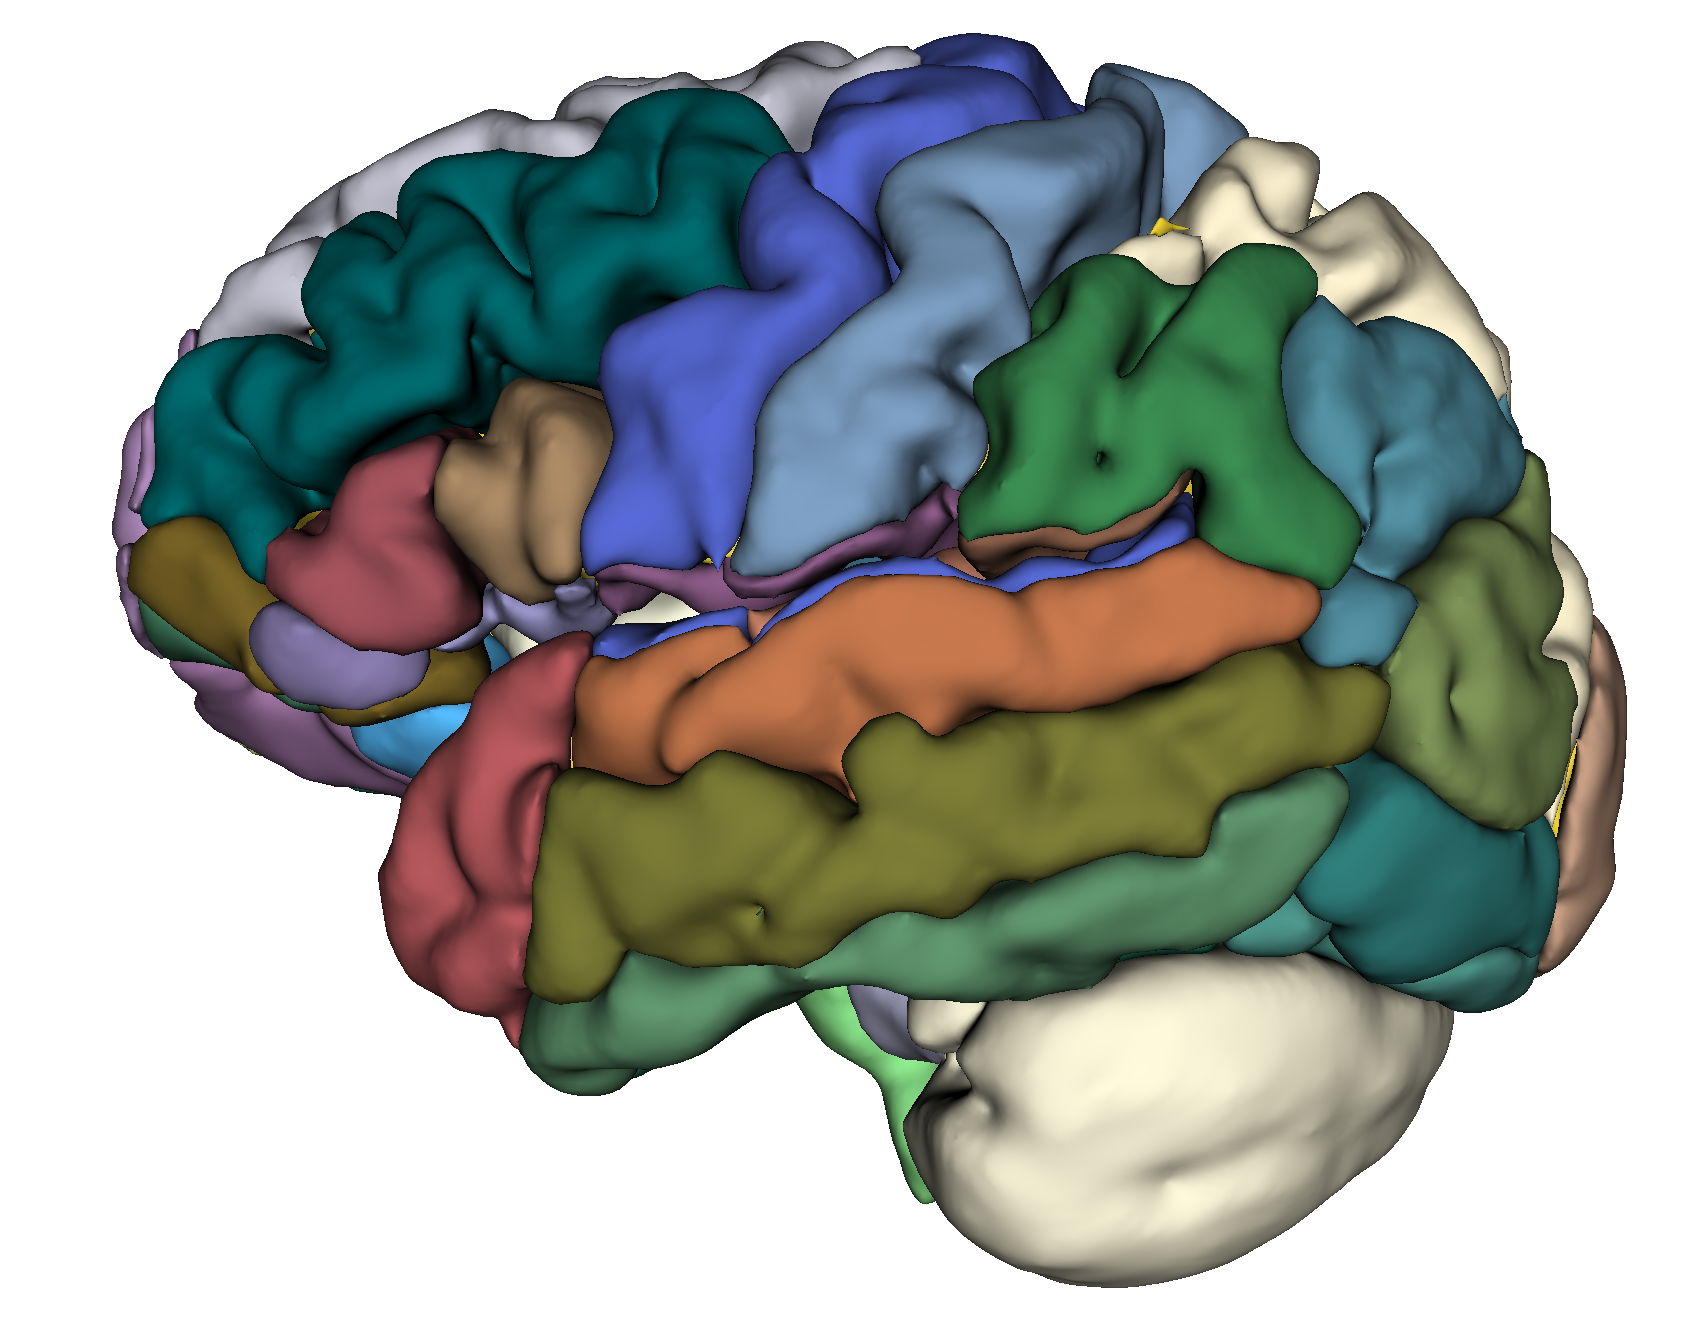

Grafik Gehirn mit Arealen in Farben

Exemplarische Darstellung eines komplett segmentierten Gehirns zur Berechnung der jeweiligen Hirnvolumina.